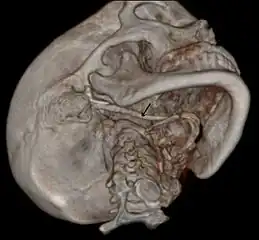

3D-reconstructed CT scan showing bilateral stylohyoid ligament ossification -

3D reconstructed CT scan showing elongated styloid process (right side)

Imaging is important and is diagnostic. Visualizing the styloid process on a CT scan with 3D reconstruction is the suggested imaging technique.[11] The enlarged styloid may be visible on an orthopantogram or a lateral soft tissue X ray of the neck.